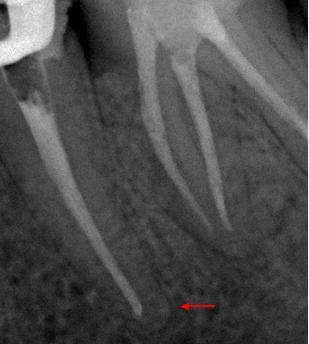

Пациент 45 лет направлен лечащим доктором на перелечивание 35 зуба.

Со слов пациента эндодонтическое лечение проводилось три года назад.

На рентгенологических снимках представлена картина до лечения, диагностический снимок и конечный результат.